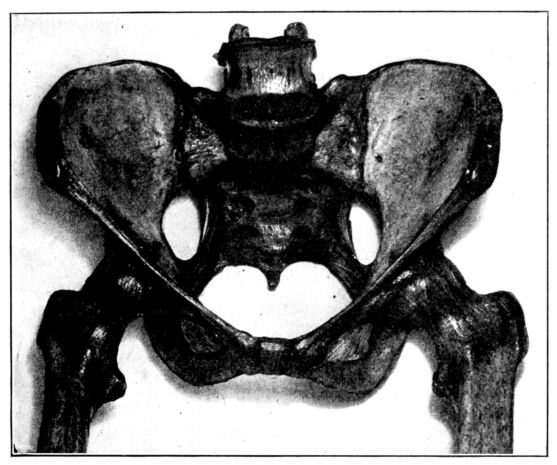

A. Normal female Pelvis.

B. Normal male Pelvis.

Fig. 1.—Normal Pelves. Note the broad, shallow, light construction of the female pelvis, A, as compared with the more massive male pelvis, B.

The normal male pelvis is deep, narrow, rough and massive as compared with the female structure (see Fig. 1.), and the angle of the pubic arch, formed by the two pubic bones, is deeper and more acute in the male than in the female skeleton.

The normal female pelvis, on the other hand, is light, broad, shallow, smooth and large, giving evidence of the infinite wisdom and skill that entered into constructing it for the high purpose it was designed to serve.